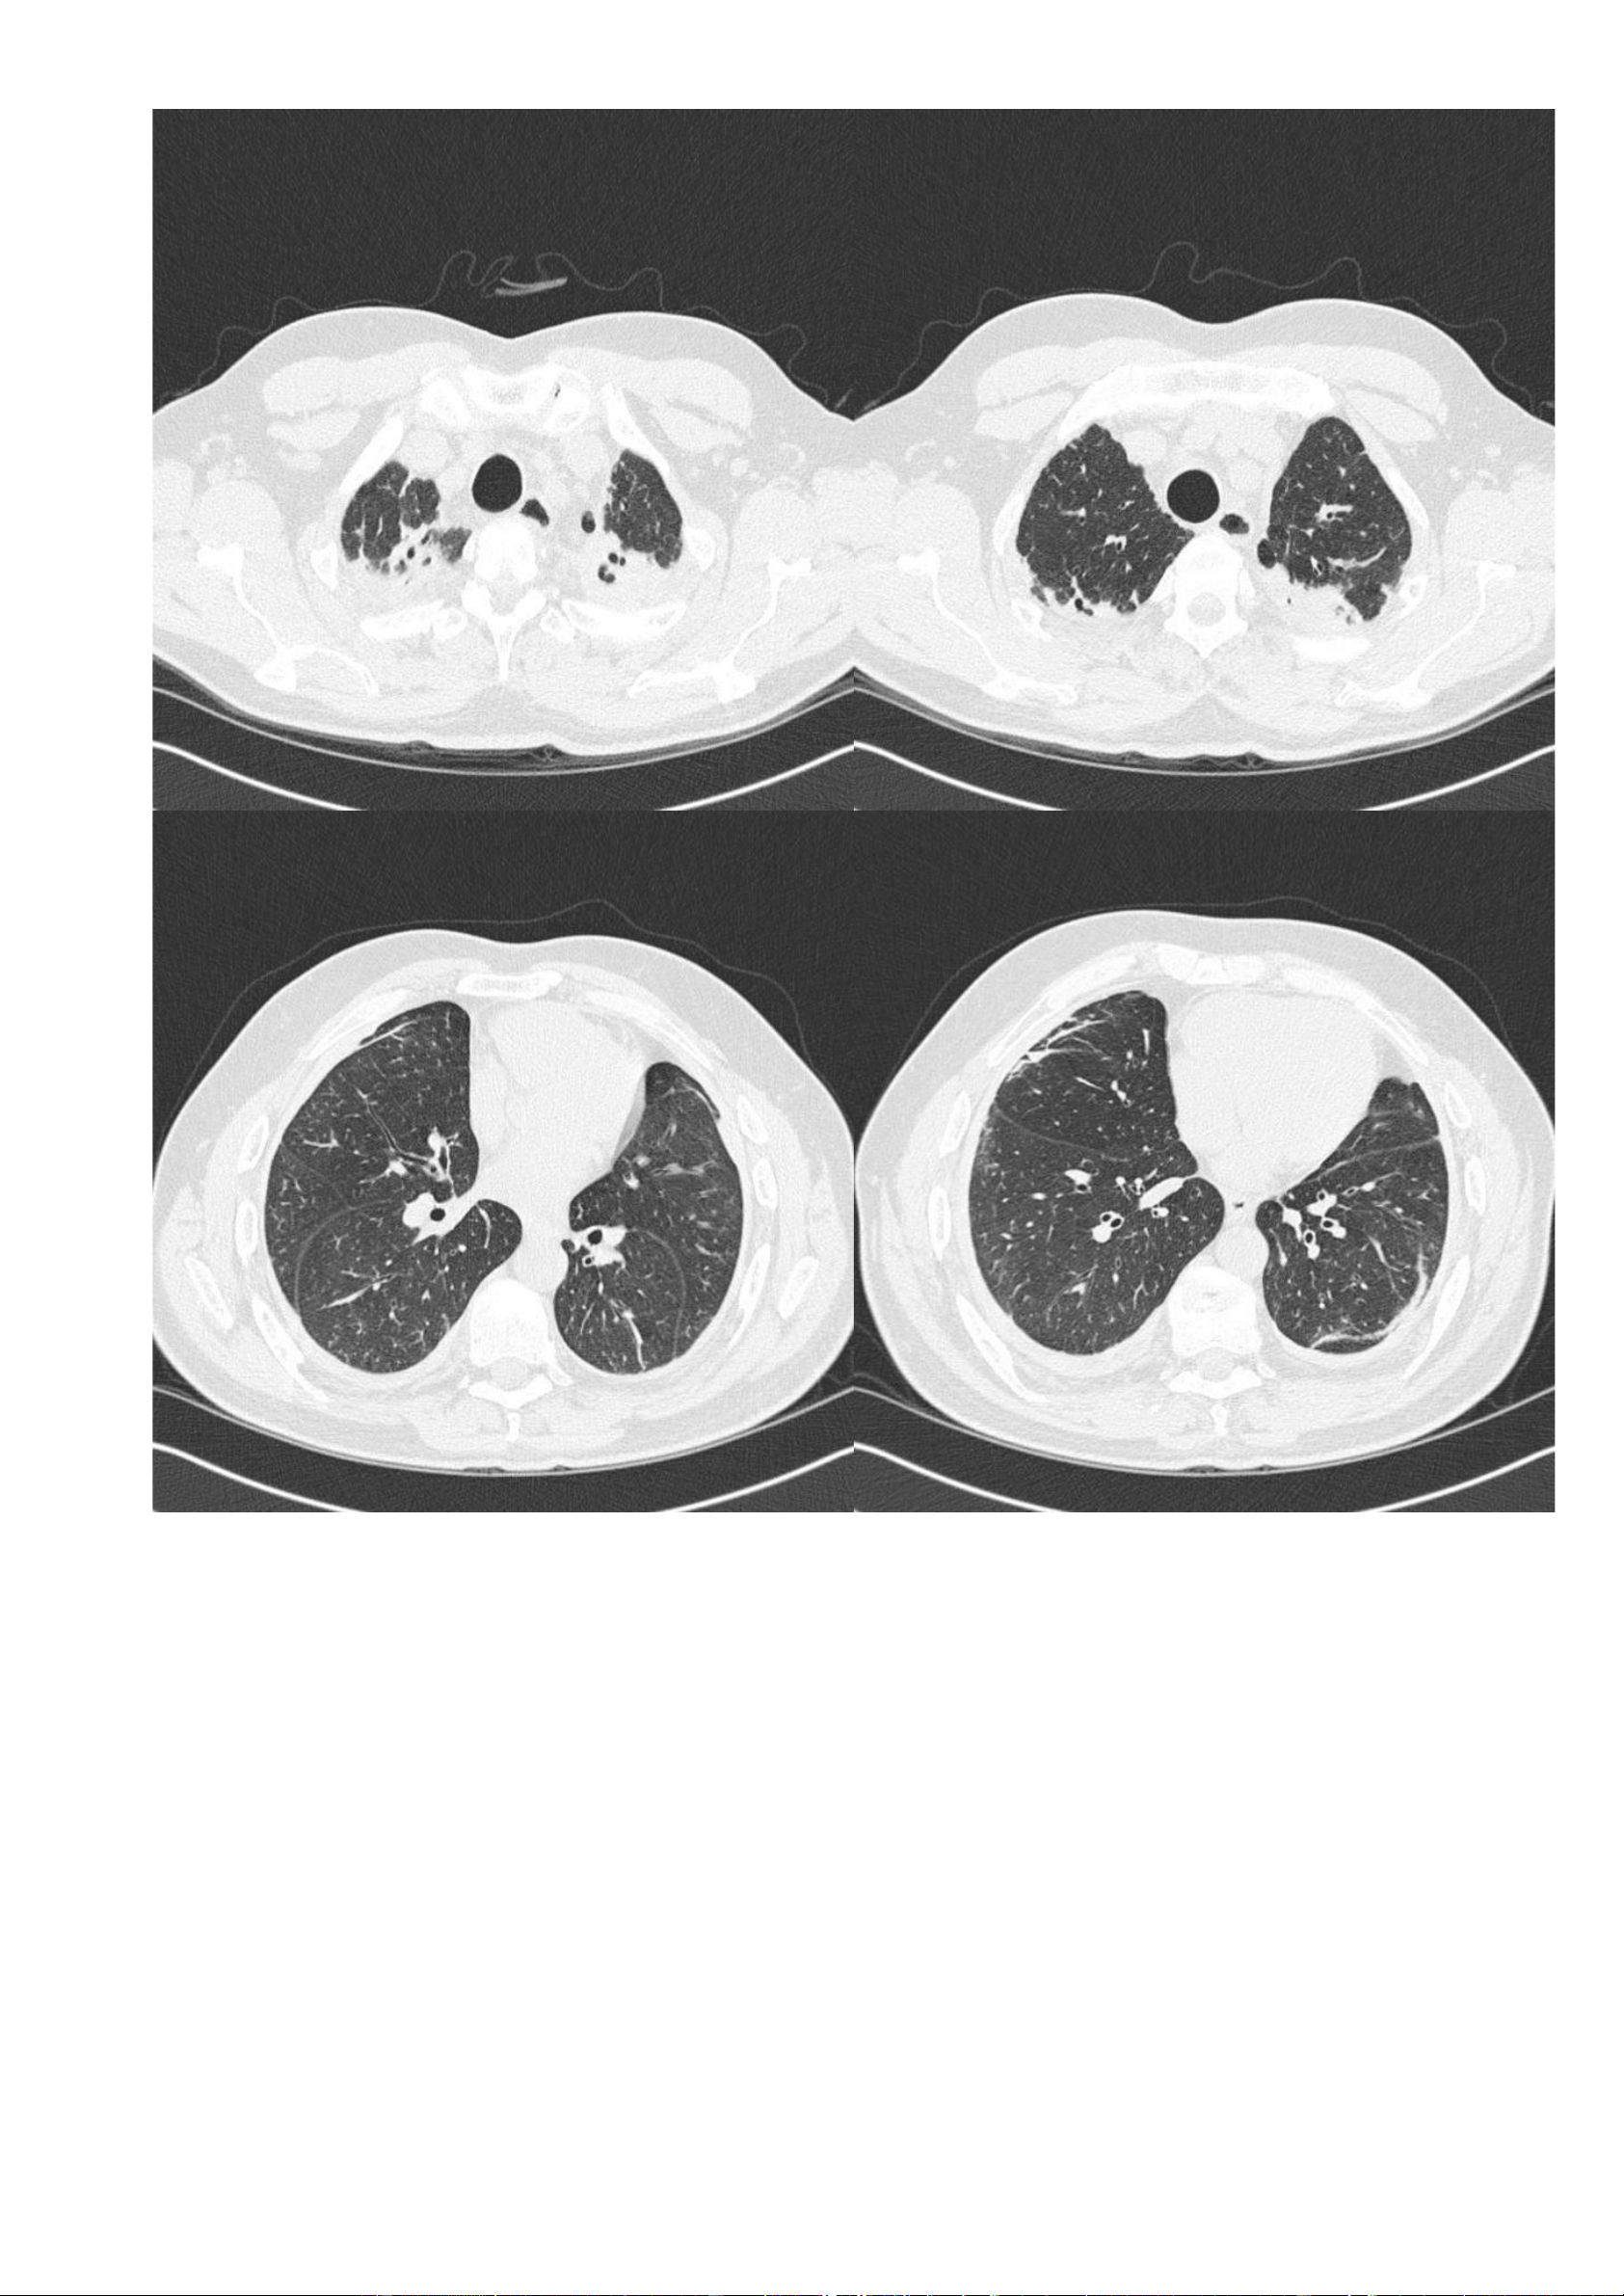

Nguồn link: https://radiopaedia.org/cases/asbestosis - Thông tin bệnh nhân: Không có. - Hình ảnh CT: + Cửa sổ nhu mô: lOMoAR cPSD| 22014077 Phan Tùng Bách

▪ Một vài dải nhu mô dưới màng phổi hai bên.

▪ Sẹo vùng đỉnh phổi hai bên.